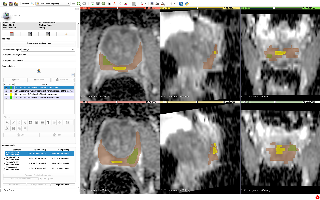

MSD前列腺分割

| 名称 | 标注内容 | 类型 | 模态 | 数量 | 标签格式 | 文件格式 | License |

|---|---|---|---|---|---|---|---|

| MSD前列腺分割 | 前列腺中央腺体及外周区域 | 分割 | 多模态核磁 | 32(训练)+16(测试) | CC-BY-SA 4.0 |